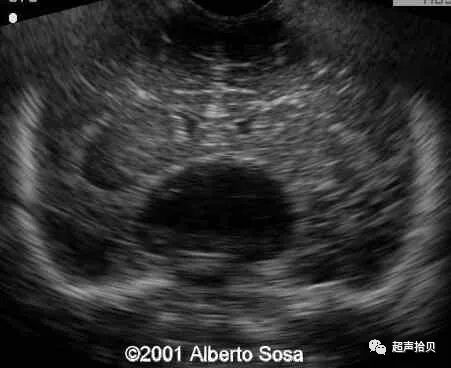

图2:冠状超声图显示位于后颅窝蛛网膜囊肿